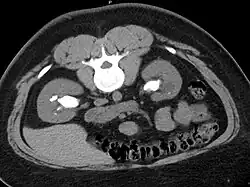

Otherwise a noncontrast helical CT scan with 5 millimeters (0.2 in) sections is the diagnostic method to use to detect kidney stones and confirm the diagnosis of kidney stone disease.[13][47][51][52][7] Near all stones are detectable on CT scans with the exception of those composed of certain drug residues in the urine,[53] such as from indinavir. Calcium-containing stones are relatively radiodense, and they can often be detected by a traditional radiograph of the abdomen that includes the kidneys, ureters, and bladder (KUB film).[53] Some 60% of all renal stones are radiopaque.[51][54] In general, calcium phosphate stones have the greatest density, followed by calcium oxalate and magnesium ammonium phosphate stones. Cystine calculi are only faintly radiodense, while uric acid stones are usually entirely radiolucent.[55]

Bilateral kidney stones can be seen on this KUB radiograph. There are phleboliths in the pelvis, which can be misinterpreted as bladder stones.

Bilateral staghorn calculi as seen on CT